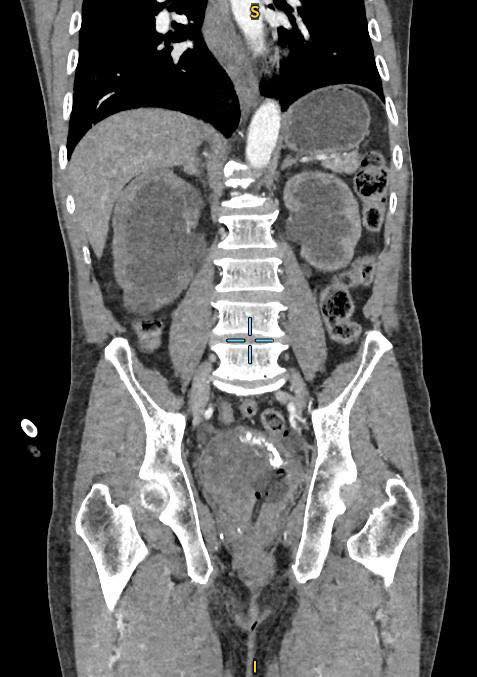

Hình ảnh CT phát hiện bướu bàng quang và thận ứ nước. Ảnh: BVCC

Tại đây, các bác sĩ khoa Ngoại Tiết Niệu đã thực hiện các cận lâm sàng chẩn đoán, ghi nhận người bệnh có bướu bàng quang to, khối u đã xâm lấn và chèn ép hai niệu quản gây thận ứ nước độ III, kèm suy thận. Ông N. được đặt ống sonde tiểu, hút ra một túi nước tiểu màu máu đỏ sậm.